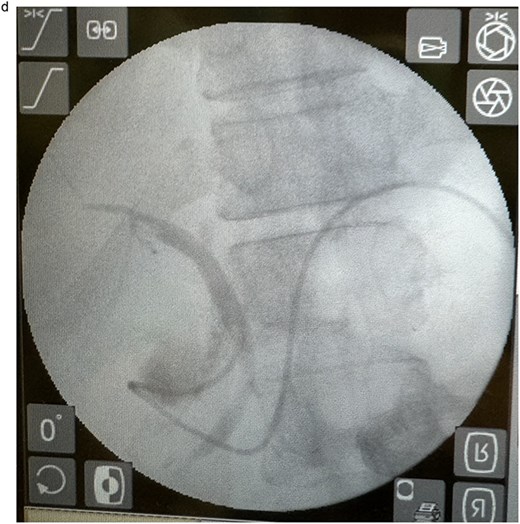

In view of the ongoing leakage and the hostile operative field, a third intervention was undertaken on postoperative day 24 following the second surgery. After multidisciplinary discussion, a combined surgical–endoscopic approach was undertaken in collaboration with internal medicine specialists. Intraoperative findings revealed dense adhesions from prior surgeries and a 0.5-cm perforation at the proximal duodenal stump, located near the ampulla of Vater. Initial endoscopic retrograde cholangiopancreatography (ERCP) was unsuccessful due to limited ampullary access; thus, EUS-CDS with ENBD placement was performed as an alternative strategy. From the duodenal bulb, the common bile duct (CBD) measured 4.7 mm on EUS, and Doppler confirmed no intervening vessels (Figs 4a and 4b). A 19-gauge EZ Shot 3 needle (Olympus) was used to puncture the extrahepatic bile duct, and bile aspiration followed by contrast injection confirmed correct positioning (Fig. 4c). A VisiGlide 2 angled guidewire (0.025 inch) was advanced into the right intrahepatic duct, and the tract was dilated using an ES dilator. A 7-Fr ENBD catheter was subsequently deployed across the choledochoduodenostomy under fluoroscopic guidance, achieving effective biliary drainage (Figs 4d and 4e). In addition, a 16-Fr Foley catheter was inserted into the duodenal perforation as a duodenostomy tube (Fig. 4f) for external drainage, and six closed wound vacuum drains were placed for peritoneal irrigation and drainage.

Schematic illustration of EUS-CDS with placement of a 7-Fr ENBD catheter into the right intrahepatic duct.